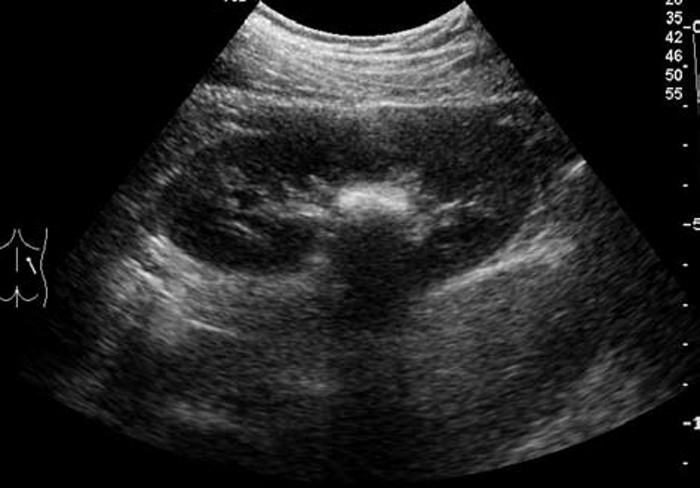

3. 鹿角状结石:大而分叉,形态不规则,超声往往仅显示局部突起的表面,呈几个孤立的强光团或弧形强回声带,像多个结石,但连续扫查可出现互相连续的一体。

典型病例

患者,男,12岁,因运动后多次突发腹痛,腹痛不能缓解并伴有恶心,面色苍白来院就诊,尿常规检查可见红细胞。超声检查显示:双肾大小形态大致正常,轮廓清,包膜光滑,实质回声尚均,呈低回声。右肾未见明显分离,左肾集合系统分离约1.1cm,左肾内可见0.9cm×0.7cm强回声,后方有声影。

超声提示:左肾集合系统分离,左肾结石。